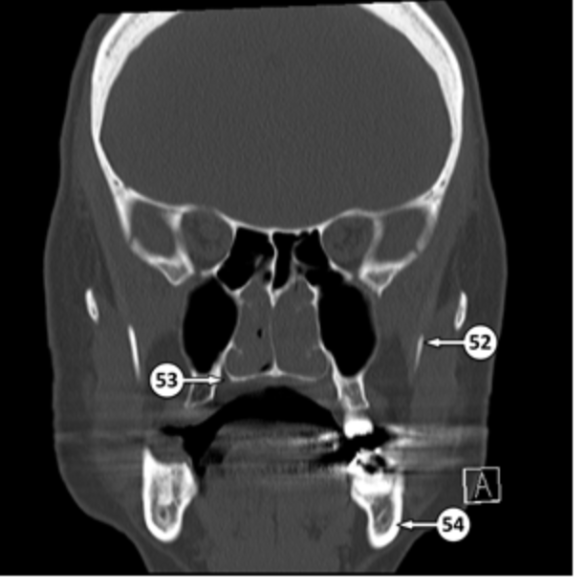

coronoid process

what is 52

identify the structure